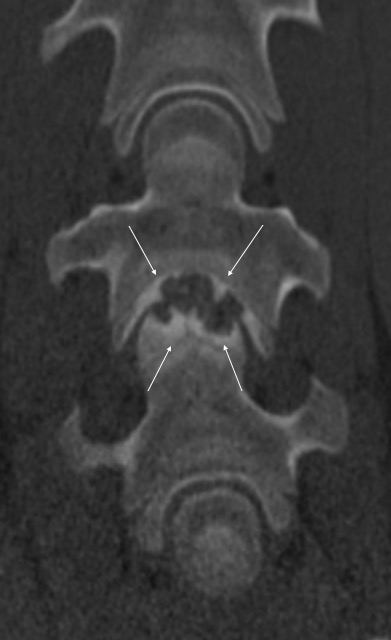

Pokud neurologické vyšetření potvrdí ataxii (stupeň 1–5), je potřeba stanovit její přesnou příčinu. Nejčastěji se jedná o zúžení páteřního kanálu v oblasti krčních obratlů, kde pak dochází k útlaku míchy – Wobblerovu syndromu. Existují ale i další příčiny ataxie, které je potřeba vzít na vědomí, například vrozené abnormality krčních obratlů (vertebrální malformace), úrazy krční páteře, nádory, virové infekce (EHV), bakteriální infekce (abscesy, záněty meziobratlových plotének a kostí) (obr. 2a, b, c), parazitární infekce nebo některé toxiny.

Obrázek 2a, b: Hříbě s ataxií a horečkou způsobenou zánětem kostí obratlů C6–C7. Na CT je jasně patrné výrazné poškození kostí v důsledku infekce (bílé šipky). Na obrázku 2b je stejný případ z jiného pohledu